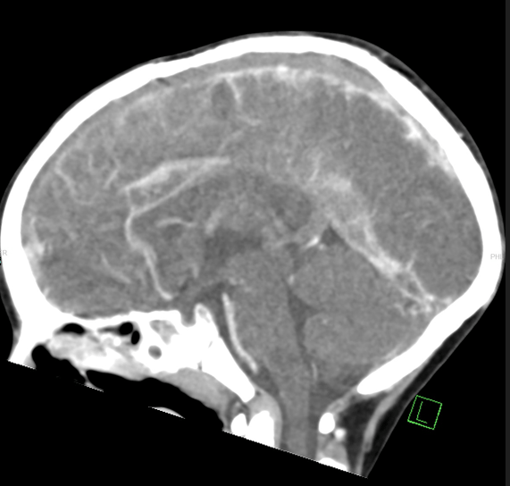

בבית החולים עבר הילד בדיקות הדמיה כולל CT וכן בדיקות מעבדה, ואז התברר שהוא סובל מפקקת סינוס ורידית מוחית - CVST (קיצור של cerebral venous sinus thrombosis), סוג נדיר של שבץ מוחי שמתרחש כאשר נוצר קריש דם בסינוסים הוורידיים של המוח. הקריש מונע מהדם להתנקז אל מחוץ למוח. כתוצאה מכך מצטבר לחץ בכלי הדם, מצב שעלול להוביל לנפיחות ולדימום במוח ודורש התערבות מיידית. "מדובר במצב רפואי נדיר שלפי הספרות הרפואית הוא מהווה סביב אחוז אחד מכלל מקרי השבץ", אומר ד"ר בורודצקי.

ד"ר בורודצקי וצוות יחידת צנתורי מוח ביצעו את הצנתור, שכלל פתיחה של כלל החסימות והוצאת קרישי דם רבים שנוצרו. הצנתור עבר בהצלחה והילד הועבר להמשך השגחה ואשפוז ביחידה לטיפול נמרץ ילדים, אולם כעבור יומיים התברר ששוב נוצרו חסימות חדשות במערכת הניקוז התוך-גולגולתית. "לצערנו, המצב שלו לא השתפר לאחר הצנתור הראשון, והפרכוסים לא פסקו. בבדיקת MRI ראינו שהחסימה חזרה שוב", מסביר ד"ר בורודצקי. בניגוד לסוג השבץ הנפוץ יותר, שנגרם כתוצאה מקריש דם בעורק שמוביל דם למוח, בשבץ מוחי ורידי קיים קושי להצליח "לנקות" את כל קרישי הדם שנוצרו. "אמורים בדרך כלל להמיס את קרישי הדם הנותרים עם תרופה, אך היא לא פעלה כצפוי, ולכן נוצרה חסימה שנית".